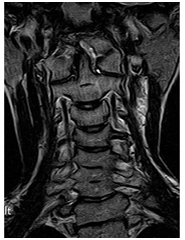

Rheumatoid arthritis atlanto-axiális közös.

Mr képet spondylosis, extrudált lemez C3-C4, C4-C5, C5-C6, C6-C7.